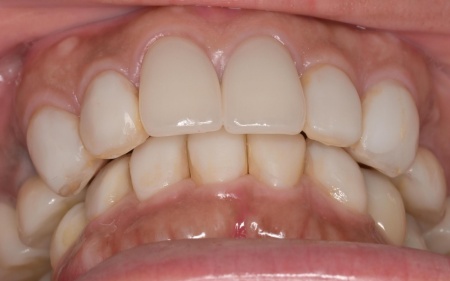

治療後

最初に前歯の位置と噛み合わせの高さを整えるための矯正治療を行い、その後、被せ物による治療で噛み合わせと審美性を回復する方法を提案しました。

矯正期間終了後は、被せ物による治療に移行します。

上顎の前歯2本ずつと奥歯4本(左右中切歯・第2小臼歯・第1大臼歯)、下顎の奥歯7本(左第1小臼歯・左右第2小臼歯・第1大臼歯・第2大臼歯)には、見た目が自然なセラミックの被せ物「ジルコニアクラウン」を装着しました。

ジルコニアは、金属を使わないため金属アレルギーの心配が少ない点、人工ダイヤモンドと呼ばれるほどの強度をもち噛む力の強い奥歯にも適している点がメリットです。

加えて、上前歯4本(左右側切歯・犬歯)と下前歯5本(左右中切歯・側切歯・右下犬歯)は、ダイレクトクラウンによる修復を行いました。

最後に、見た目や噛み合わせに問題がないかを確認し、治療を終了しました。